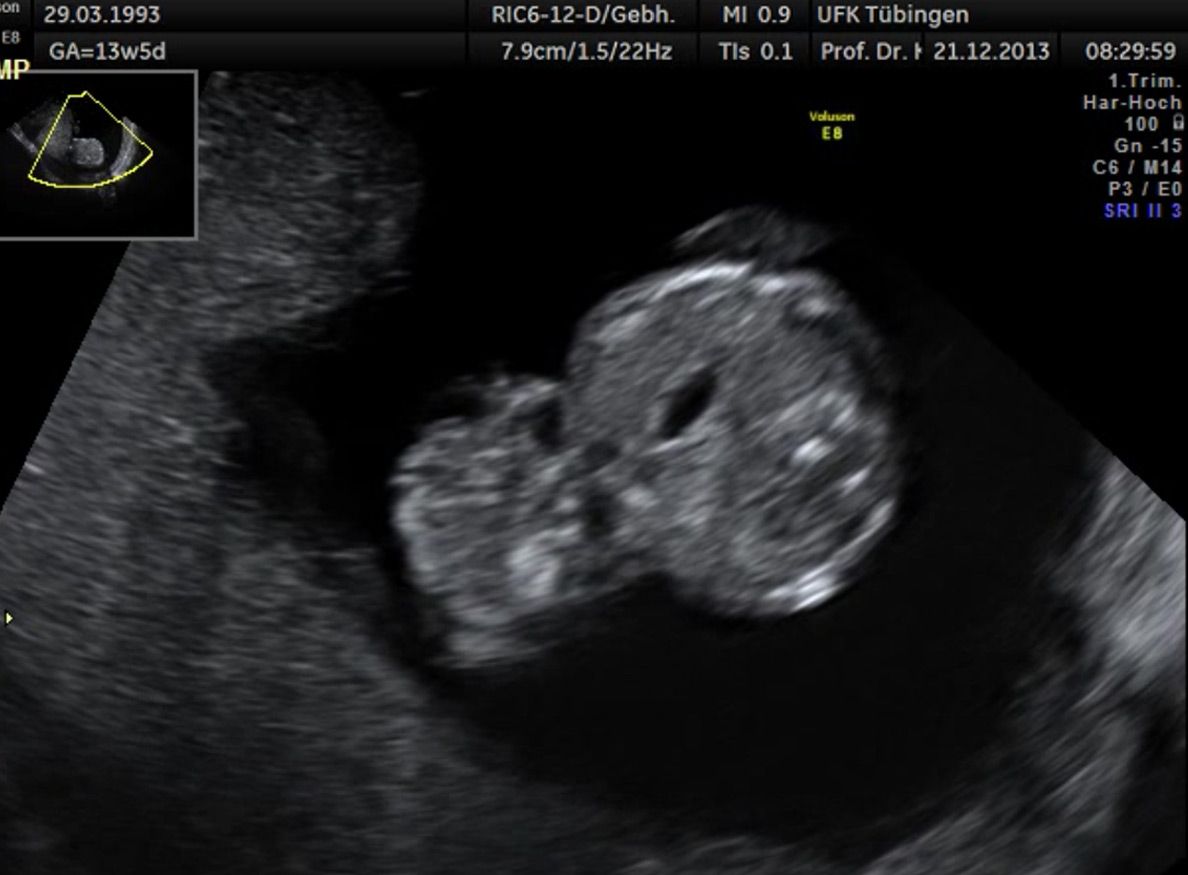

Im Rahmen des Ersttrimester-Screenings untersuchen wir die Organe des Feten mittels Ultraschall. Dabei machen wir auch gerne ein Bild für Sie.

Obwohl der Fet zu diesem Zeitpunkt erst zwischen 5 und 8cm groß ist, lassen sich bereits etwa die Hälfte aller schwerwiegenden Fehlbildungen erkennen bzw. ausschließen. Sollten wir eine Auffälligkeit sehen, werden wir mit Ihnen den Befund und das weitere Vorgehen ausführlich besprechen.

Die eigentliche Organuntersuchung findet um die 20.SSW (zweites Screening) statt. Das Ersttrimester-Screening und das zweite Screening sind sich ergänzende Untersuchungen und ersetzen sich gegenseitig nicht.